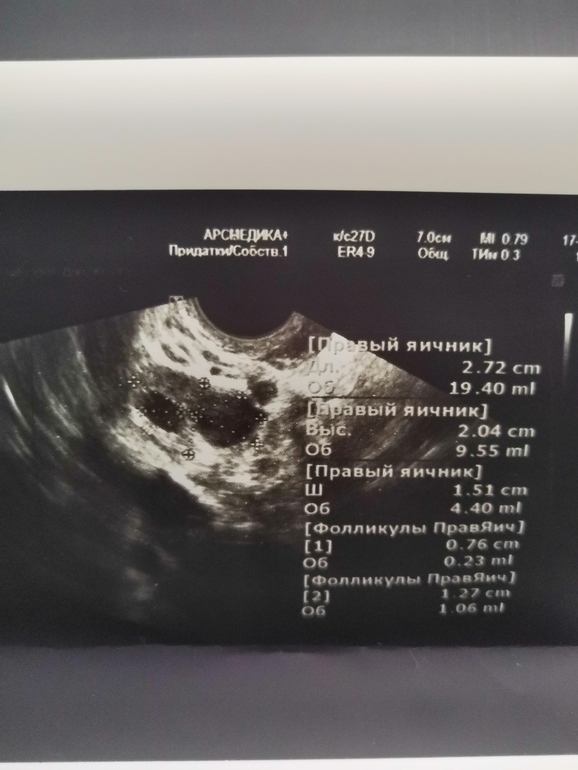

Суть в том, что я в этом месяце ходила на фолликулометрию. На 7 дц вот такая картина  врач сказал что есть большой шанс на правый яичник.

фолликул не лопнул. Месячные через 6 дней, уже и не лопнет 😔Это киста? На жёлтое тело не похоже. И почему в размере стал меньше? Я в печали, так надеялась на этот месяц....

фолликул не лопнул. Месячные через 6 дней, уже и не лопнет 😔Это киста? На жёлтое тело не похоже. И почему в размере стал меньше? Я в печали, так надеялась на этот месяц....

Про это ничего не сказал доктор. Сказал не пойму что это. Типо если это жёлтое тело, то оно очень странное. Типо вокруг этого пузыря толстый слой какой то 🤷🏼♀️

А почему это не ЖТ? Может и оно? А если киста фоликулярная, то она больших размеров, а тут нормальные.

Врач сказал если это жёлтое тело, то оно очень странное. Типо вокруг этого пузыря толстый слой какой то

Он регрессирует, судя по узи. Раз не лопнул, значит, и ЖТ нет. Ждите месячных